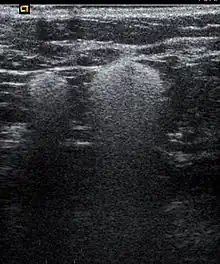

Snowball like hyperechogenic axillary lymph nodes in a woman with silicone implants removed due to complications | |